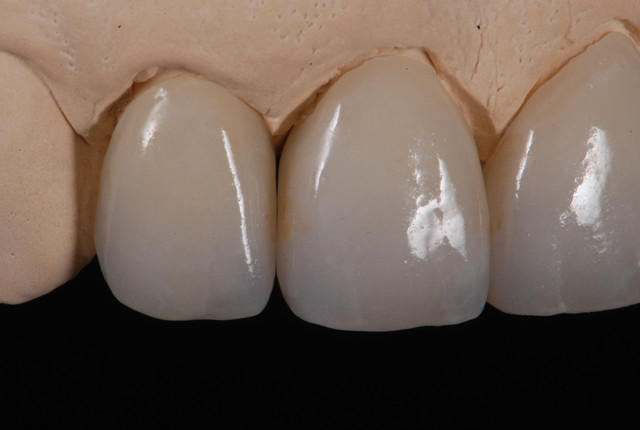

E.max crown try in 280713

#Togias 190713 nora